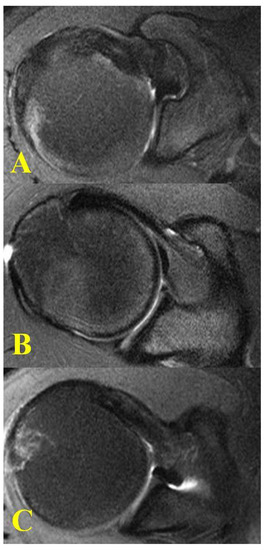

- Goutallier, D.; Postel, J.; Bernageau, J.; Lavau, L.; Voisin, M. Fatty muscle degeneration in cuff ruptures. Pre- and postoperative evaluation by CT scan. Clin. Orthop. Relat. Res. 1994, 304, 78–83. [Google Scholar] [CrossRef]

- Osti, L.; Buda, M.; Del Buono, A. Fatty infiltration of the shoulder: Diagnosis and reversibility. Muscles Ligaments Tendons J. 2013, 3, 351–354. [Google Scholar] [CrossRef]